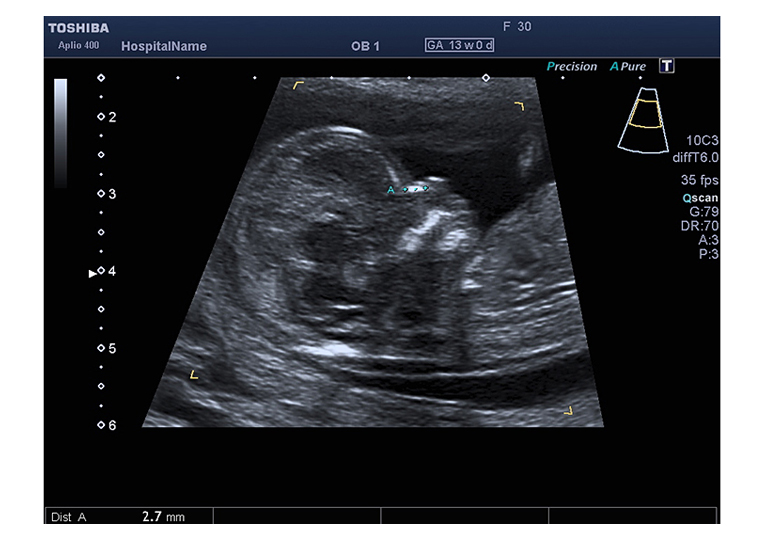

Bei dieser Nackentransparenz handelt es sich um eine Flüssigkeitsansammlung im Nacken des Feten, welche bei jedem Kind mehr oder weniger in dieser Phase der Schwangerschaft auftritt. Je nach Grösse des Kindes sind 0,8 bis 2,5 mm „Nackentransparenz“ normal. Eine Verbreiterung dieser „Nackentransparenz“ kann ein Hinweis auf eine Chromosomenstörung, einen Herzfehler oder eine andere Erkrankung des Feten sein. Jedoch können auch gesunde Kinder eine verbreiterte Nackentransparenz aufweisen. Es sind oft nur wenige zehntel Millimeter, um welche die Nackentransparenz bei einem „auffälligen“ Kind vergrößert ist. Daher ist für die Messung ein gutes Ultraschallgerät, Erfahrung und eine spezielle Ausbildung nötig. Generell gilt jedoch: Je breiter die Nackentransparenz, je größer die Wahrscheinlichkeit für ein genetisch oder organisch erkranktes Kind.

Weitere Merkmale, welche in die Risikoberechnung des Kindes einbezogen werden können, sind die Darstellung des kindlichen Nasenbeins, Besonderheiten im Bereich des kindlichen Herzens und weitere organische Auffälligkeiten. Das individuelle Risiko einer jeden Schwangeren, welches neben dem Alter der Schwangeren auch die Nackentransparenz und weitere Ultraschallmarker berücksichti gt, kann dann mittels Computer berechnet werden.